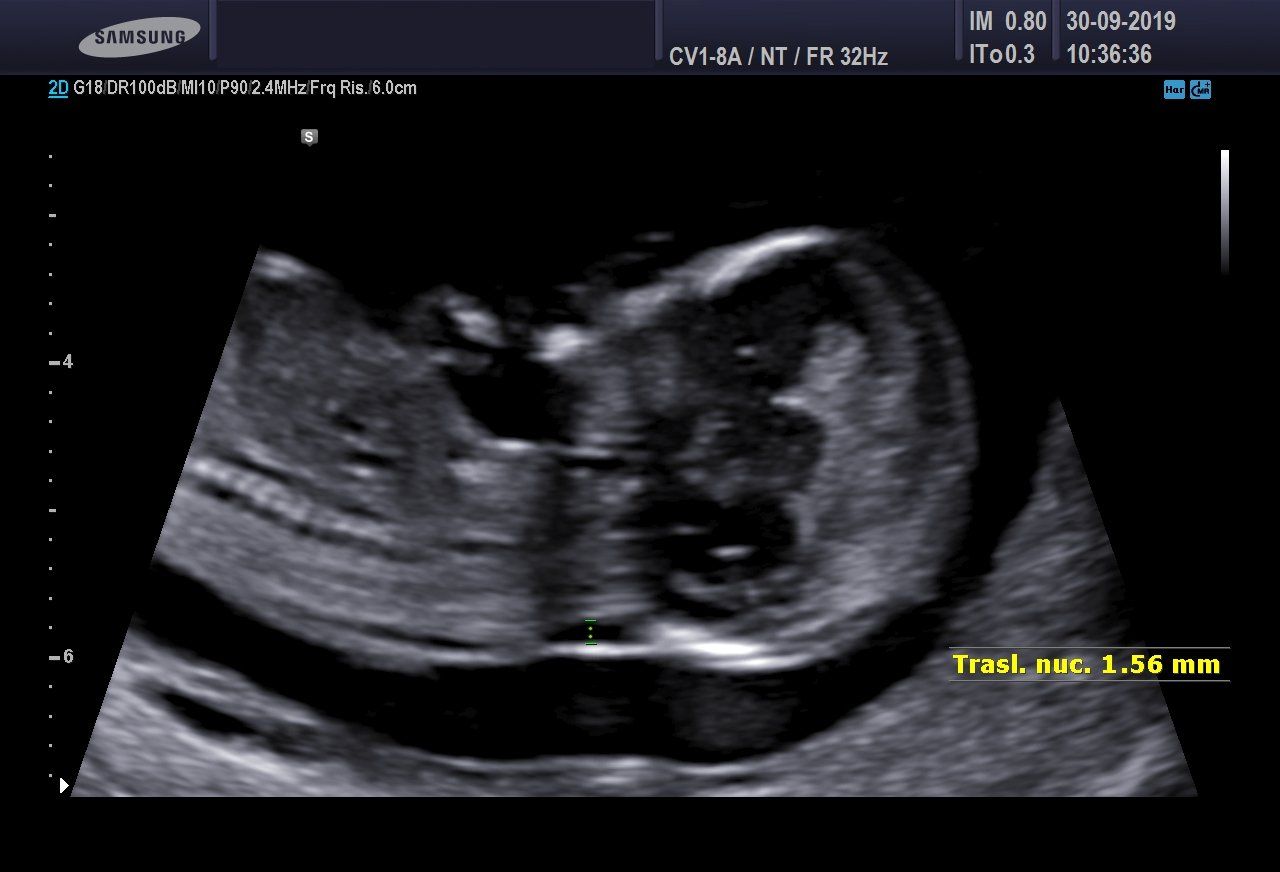

Screening del I Trimestre

È in atto il metodo più attendibile e non invasivo nel corso della gravidanza per valutare il rischio di avere un bimbo con un problema cromosomico, come per esempio la Sindrome di Down.